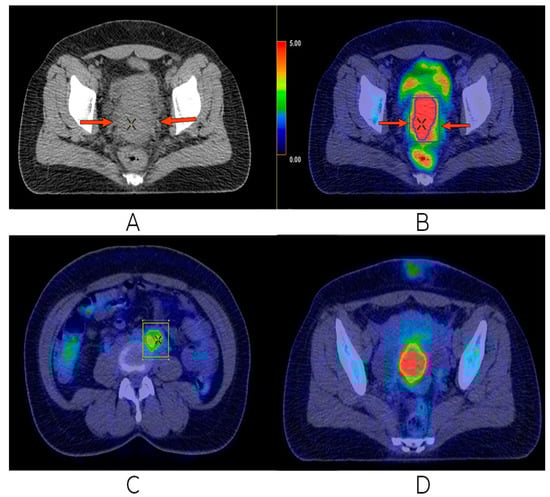

2.2. Imaging, Treatment Strategies, and Response